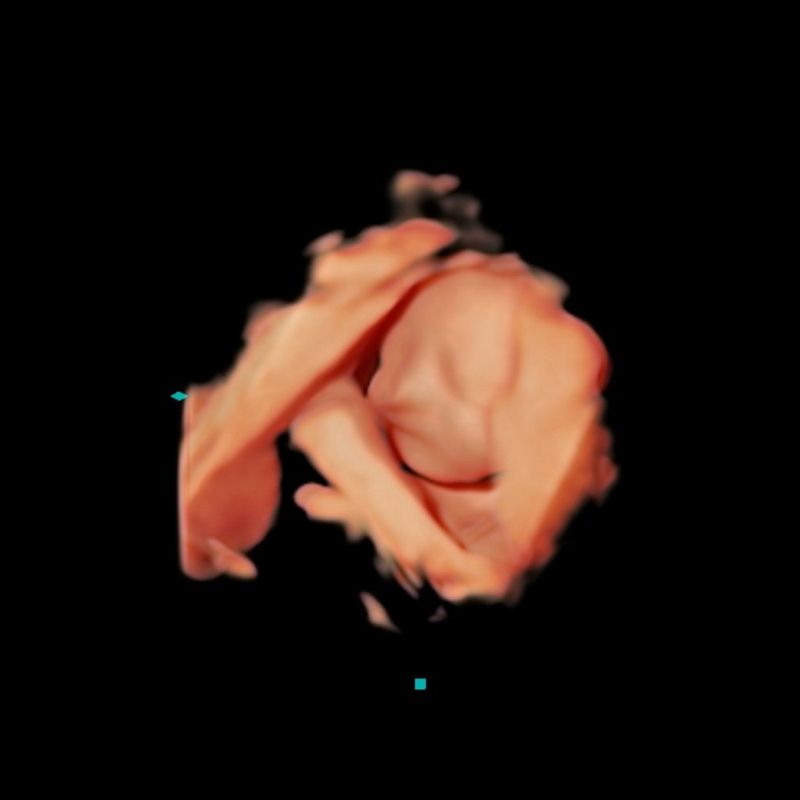

Al centro di quest'immagine si distingue chiaramente il volto di un feto. Immersa in uno spazio scuro e avvolgente, la testa priva di capelli è leggermente inclinata verso sinistra e rivolta verso il basso. Gli occhi e la bocca sono chiusi, mentre il piccolo mento rotondo poggia delicatamente sulle braccia incrociate. Ai lati dell'immagine si intravedono i margini della placenta.

Nonostante lo sfondo nero, l'attenzione di chi guarda è attratta dalle forme lisce e color sabbia al centro. Il piccolo naso delicato e i lineamenti rilassati del viso, insieme alle braccia piegate, suggeriscono tranquillità, forse un sonno placido. La composizione ha un'aura eterea, quasi come se la figura stesse fluttuando nello spazio. Questo effetto è accentuato dal fatto che i contorni del viso sono sfumati e indistinti, mentre striature arancioni si dissolvono nello sfondo nero. Sembra quasi che questa creatura stia dormendo in uno spazio di pace assoluta.

Quest'immagine si differenzia da altri tipi di fotografie o scansioni perché si tratta di un'immagine ecografica 3D del volto di un feto, catturata durante un'ecografia transaddominale il 13 dicembre 2023.

Sono Bill Smith, l'ecografista che ha eseguito questa scansione. Per farla, ho utilizzato il sistema Canon Medical Aplio i700. Si tratta dell'ecografia del terzo trimestre della gravidanza di Karen. Il feto è stato catturato con una nitidezza incredibile, a 29 settimane e tre giorni di gravidanza.

È una femmina, ed è la seconda figlia di Karen.

Nel caso di Karen, l'ecografia ha mostrato un andamento regolare della gravidanza. Anche se i bambini aprono gli occhi nel grembo materno, tendono a farlo più tardi nella gravidanza, e questa bambina li ha tenuti chiusi. Karen è stata tanto felice quanto rassicurata nel sentire il battito cardiaco della sua bimba.